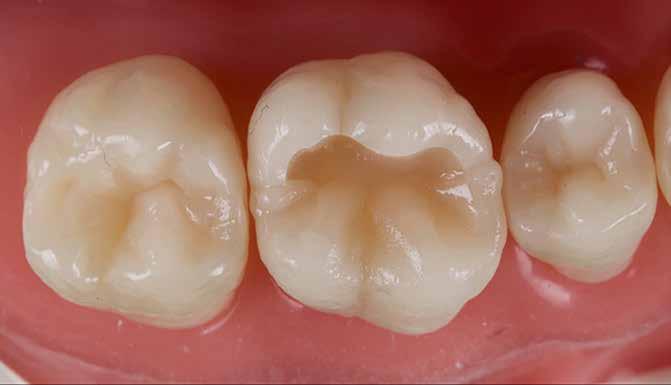

Kiindulópont: egyszerű I. osztályú rágófelszíni kavitás (3. ábra).

Általános szabály, hogy az okkluzális iránytűt csücsökről csücsökre haladva kell felépíteni, mindig a legnagyobb csücsökkel ellentétes oldalon kezdve. Mivel a felső első moláris legnagyobb csücske a mesio-palatinális, a szerző a mesio-bukkális csücskön kezdi a munkát.

A mesio-bukkális háromszöget és a marginális gerincet az adott VITA árnyalatnak megfelelő, alacsony opacitású kompozitból alakítja ki. Ezzel egyidejűleg kialakul a középső bukkális barázda (kék - laterotruzív irány) és a másodlagos mesio-bukkális anatómia (sárga - lateroprotruzív irány).

Az első réteget a „Pulse-Activation” protokoll [13] szerint kell polimerizálni gél-állapotig; ennek kettős előnye, hogy idő takarítható meg vele, másrészt csökkenti a polimerizációs zsugorodási feszültséget a restaurációban (4. a és 4. b ábra). Ezt követően a disto-bukkális háromszög és marginális gerinc kialakítása történik hasonló módon; ezzel befejeződik a középső bukkális barázda kialakítása (kék - laterotrusív mozgás), és létrejön a disto-bukkális csücsök másodlagos anatómiája (piros - lateroresurtrusív mozgás).

Megjegyzésként elmondható, hogy a középső bukkális barázda helyes pozíciója kulcsfontosságú mind a laterotrusív mozgás szempontjából, mind az okkluzális iránytű középpontjának végső helyzetének meghatározásában.

A szerző tapasztalata szerint jól használható támpont, ha gondolatban egy egyenest húzunk a mesio-bukkális csücsök csúcsa és a disto-bukkális csücsök csúcsa között, majd ezt merőlegesen elfelezzük – ez a vonal legtöbbször jól megfelel a középső bukkális barázda helyzetének (5. a és 5. b ábra)

A következő lépés a mesio-palatinális háromszög és marginális gerinc felépítése, egy kisebb bemélyedés megformázásával, amely lehetővé teszi a mediotrusiót (zöld), valamint kialakítandó az ún. Stuart-barázda is. Ezen felül a szerző egy apró, ujj-szerű kiemelkedést is megformáz a mesiális marginális gerinctől az okklúziós iránytűpont felé, amely a fekete jelölésű protrusív mozgást biztosítja (6. a és 6. b ábra).

A felépítés a disto-palatinális csücsök háromszög és marginális gerinc kialakításával fejeződik be. Fontos megjegyezni, hogy a palatinális barázda distális irányba fut, emiatt a mesio-palatinális csücsök nagyobb, mint a disto-palatinális – ez okozza az egyik leggyakoribb hibát az első moláris felépítésekor. Ezen felül pedig egy további iránytűpont vetül mesialis irányba a második moláris mesiális marginális gerincétől; ügyelni kell arra, hogy a disto-palatinális csücsök lejtői ne akadályozzák ennek a mozgásnak a mediotrusív pályáját (7. a és 7. b ábra).